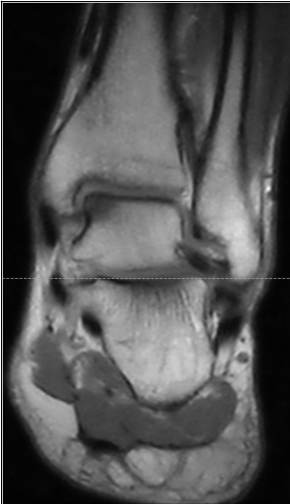

Cartilage lesion remediation, nanoperforations and Chondrofiller